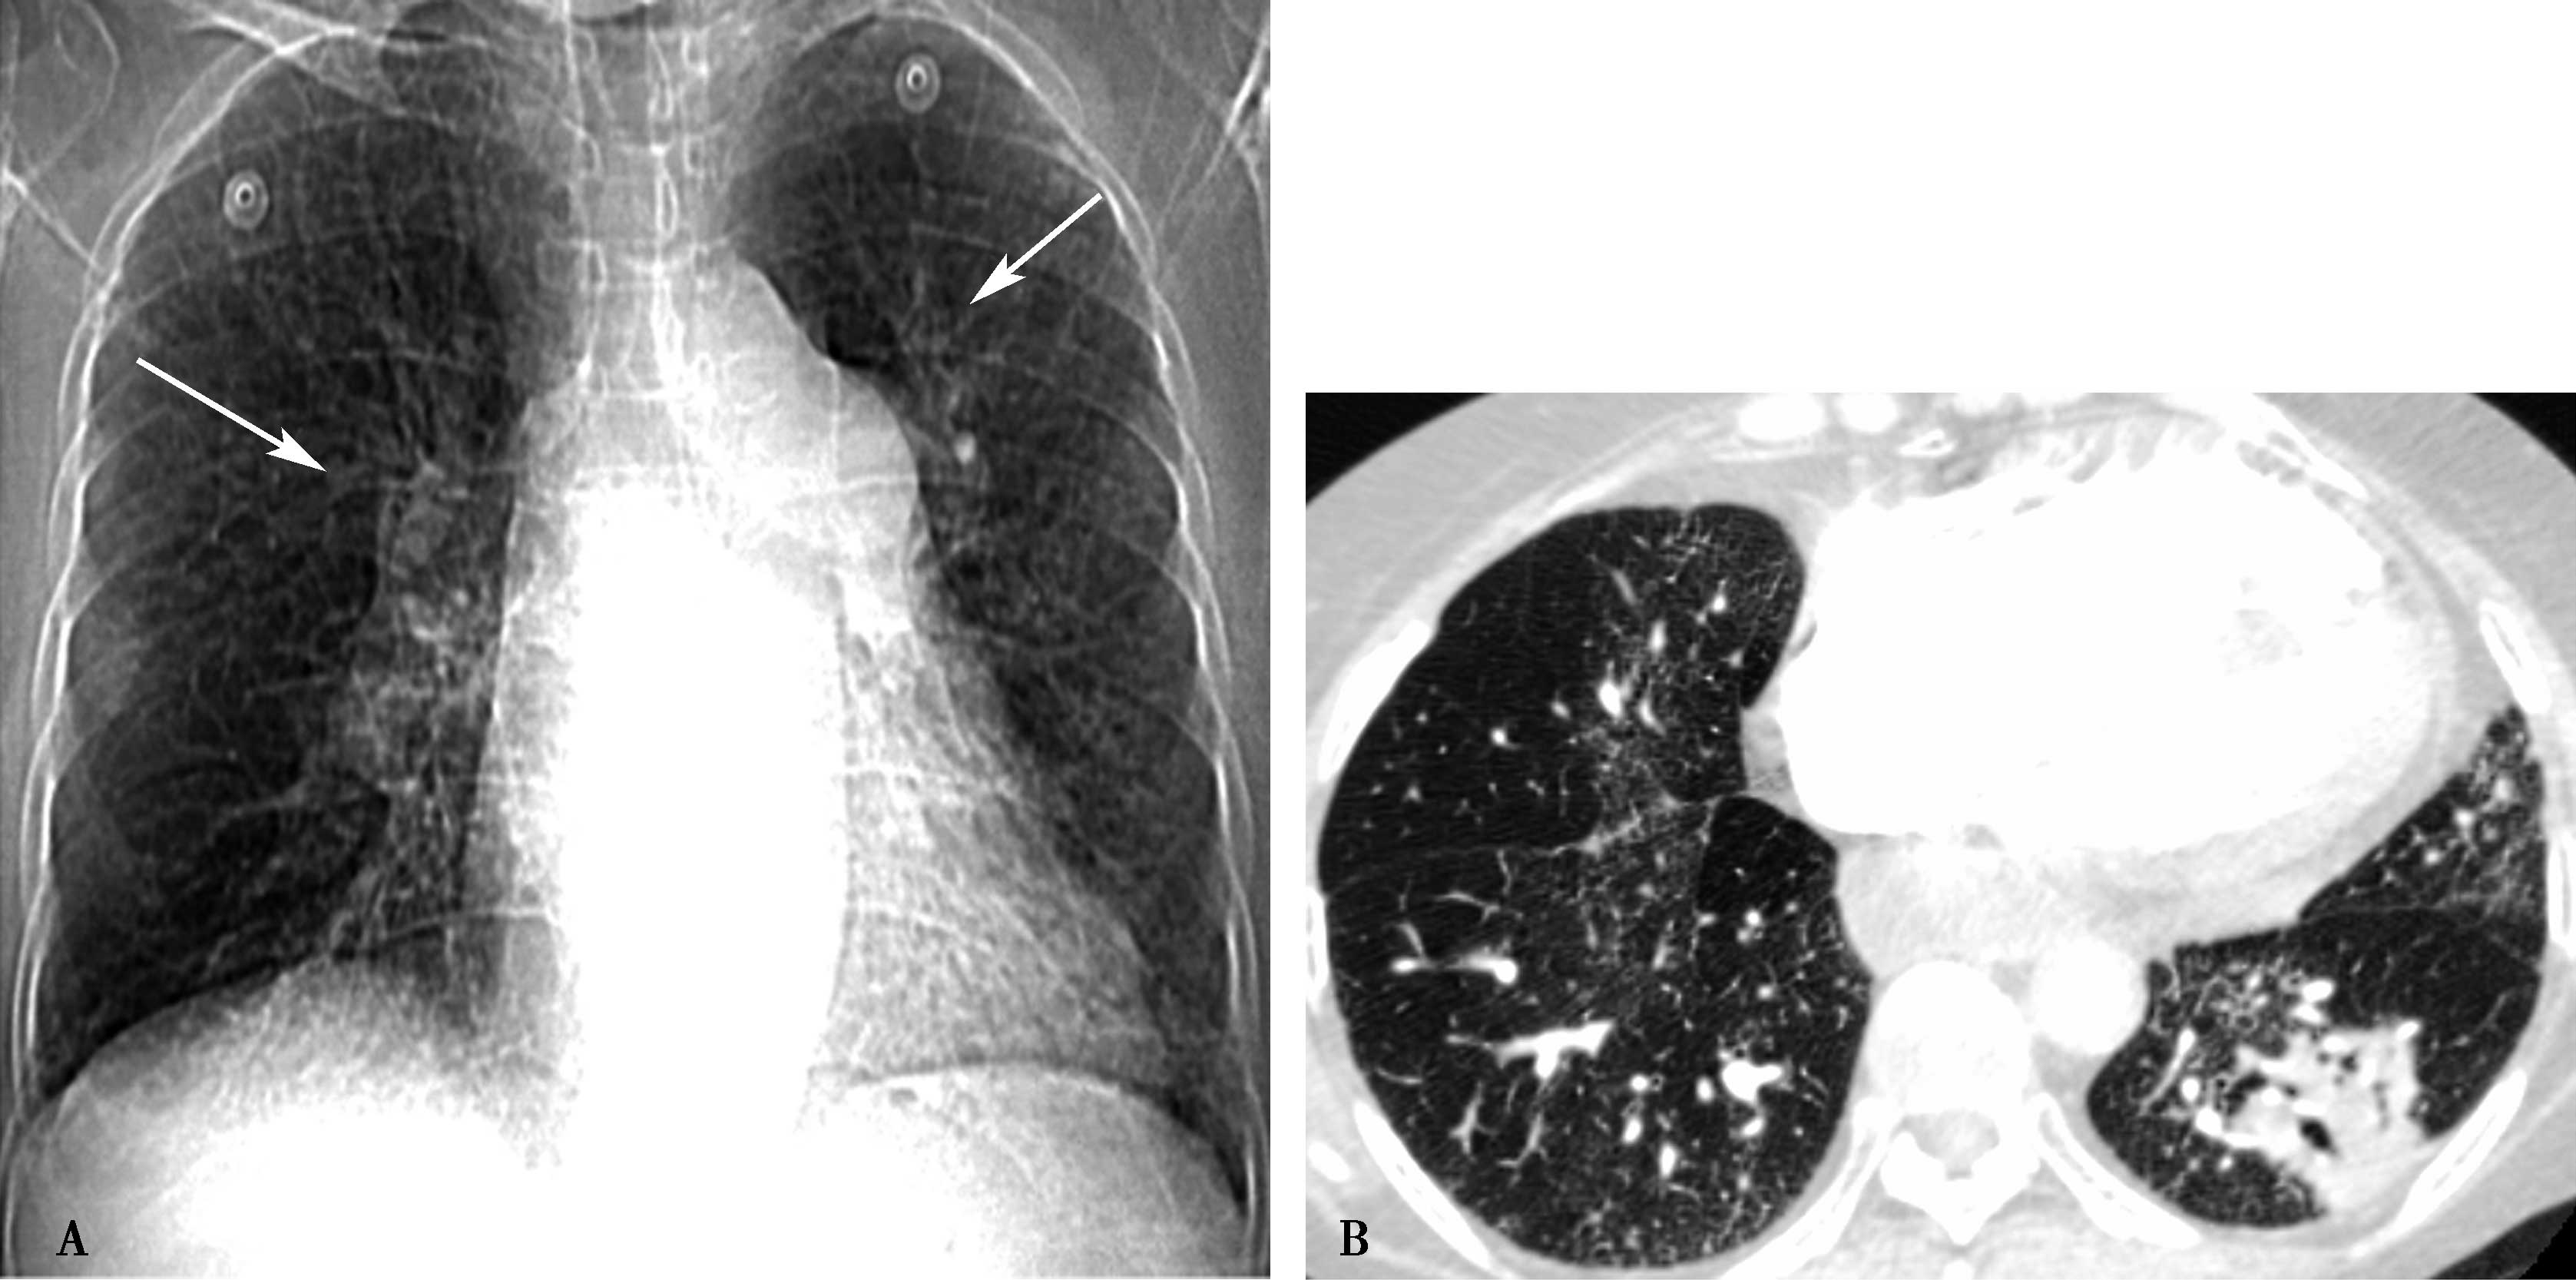

(一)肺血增多

肺动脉血流量增多,肺动脉及分支充血、扩张,又称肺充血。主要见于左向右分流或有动静脉血混合的双向分流的先天性心脏畸形,如房、室间隔缺损,动脉导管未闭,不合并肺动脉狭窄的大动脉转位、单心室畸形等。体动-静脉瘘、甲状腺功能亢进、发热、缺氧等右心排血量增加也可表现肺血增多。冠心病心肌梗死室间隔穿孔者也可见肺血增多。

X线表现见图7-1-7。

图7-1-7 X线表现

A.轻度增多(右下肺动脉轻度增宽↑);B.中度增多(右下肺动脉中度增宽↑,肺内、中带血管增粗);C.高度增多(右下肺动脉高度增宽↑,肺内、中带血管增粗)

1.肺血管(动脉)纹理增粗、增多,可波及中外带肺野,增粗的纹理边缘清楚。

2.肺门影增大,主要是动脉部分增粗增大,肺动脉段突出,搏动增强,肺门舞蹈征。

3.肺野透过度正常。

(二)肺血减少

肺动脉血流量减少,肺动脉分支变细及稀少,又称肺缺血,主要见于右心排血受阻疾患,如肺动脉瓣狭窄、心脏三联症、四联症、肺动脉闭锁等。此外,见于肺动脉血栓栓塞,一侧肺动脉发育不全或缺如,以及各种病因引起的重度肺动脉高压,可以显示中心肺动脉扩张,而外围肺血减少。

X线表现见图7-1-8。

图7-1-8 X线表现

A.轻度肺血减少(右下肺动脉稍细↑);B.中度肺血减少(右下肺动脉中度变细↑);C.重度肺血减少(右下肺动脉明显变细,或不可见↑)

1.肺动脉血管纹理纤细、稀疏。

2.肺门阴影动脉缩小(右下肺动脉变细,图7-1-8↑),搏动减弱或呈静止状态。肺动脉段可因不同情况而表现突出(见于肺动脉瓣狭窄、肺动脉高压),或平直或凹陷(见于右心室流出道狭窄)。肺动脉瓣狭窄可表现两侧肺门(动脉)不对称,左侧大于右侧。

3.肺野透亮度增加。

4.严重的肺动脉狭窄或闭锁,可出现侧支循环,X线表现为肺内可见粗乱血管的网状阴影,扭曲、粗细不均,走向无规律。